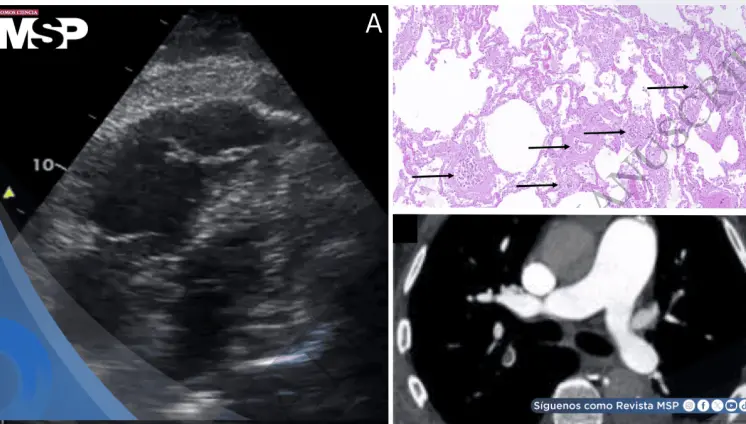

Shock obstructivo agudo por microangiopatía trombótica tumoral pulmonar en paciente con estenosis aórtica